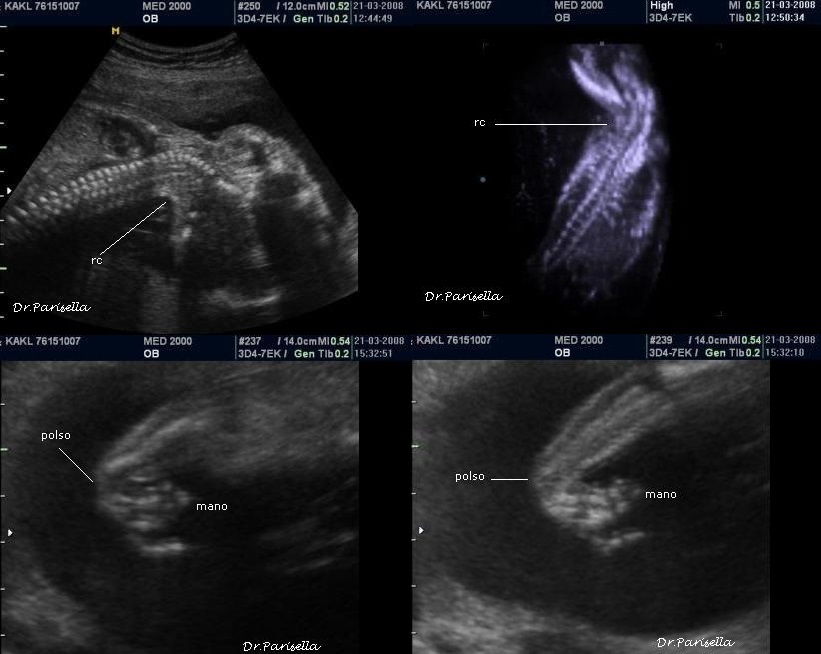

E' caratterizzata da grave ritardo di crescita intrauterino, grave microcefalia, lissencefalia tipo 3  e dismorfismi facciali consistenti in ipertelorismo, micrognazia, grave esoftalmo, anomalie auricolari, naso piatto; una caratteristica è l'edema spiccato che interessa cranio, gomiti, ginocchia, mani e piedi (si ha quasi l'impressione che le dita siano assenti); vi è inoltre assenza dei movimenti attivi fetali (SAF) e possono esservi contratture articolari (artrogriposi) caratterizzate da arti superiori ed inferiori in flessione.

I segni ecografici sono numerosi :

1. IUGR

2. microcefalia grave,

3. esoftalmo spiccato,

4. edema spiccato,

5. assenza di movimenti attivi fetali (SAF),

6. lissencefalia tipo 3,

7. micrognazia,

8. ipertelorismo,

9. idrope,

10. anomalie del SNC come agenesia del corpo calloso e ipoplasia cerebellare,

11. polidramnios.

Caratteristica ai fini diagnostici la triade: IUGR, Esoftalmo spiccato, Edema fetale.